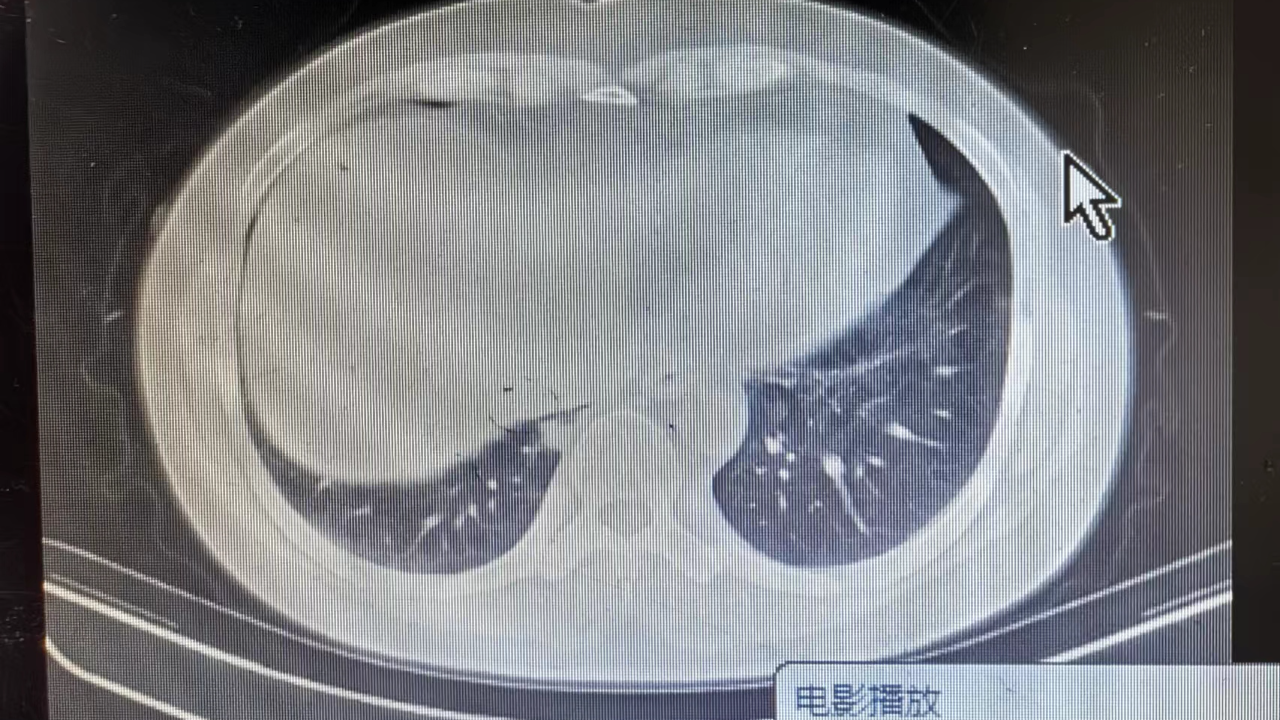

女, 50 岁,主因发现肺占位20余天于2024-06-11 17:05入院。

1.现病史:患者中年 女,患者于入院前20余天体检发现右肺占位,轻度胸闷、憋气,无发热,无咳嗽、咳痰,无胸痛,无咯血,无恶心、呕吐,无腹痛、腹泻,无抽搐及意识障碍,